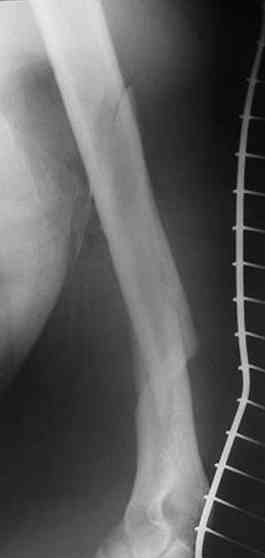

Несмотря на высокоэнергетический характер ранения, пуля не попала непосредственно в кость, а прошла рядом. Таким образом, для бедренной кости это ранение нельзя назватьв полном смысле этого слова высокоэнергетическим. К сожалению, не видно выходное отверстие. В любом случае, при таком переломе интрамедуллярный остеосинтез вполне показан. Кроме того, если пациент попал к Вам в первые часы после ранения, рана не должна рассматриваться как инфицированная. В качестве примера возможности даже более травматичной операции при таком характере перелома привожу следующий случай.

Пациент оперирован на 5-е сутки (переведен из другого лечебного учреждения)после сквозного пулевого ранения плеча и грудной клетки (непроникающее ранение той же пулей). Выполнен минимально инвазивный остеосинтез блокируемой метадиафизарной пластиной, повторная хирургическая обработка ран плеча. Заживление всех ран первичное, сращение наступило в обычные сроки.